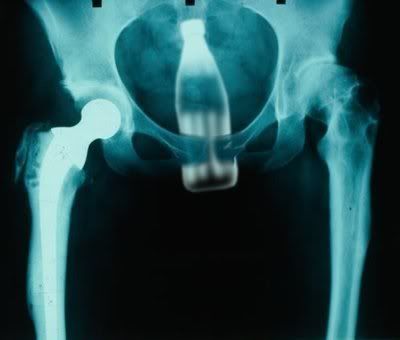

PepperTedII Really Experienced Joined Sep 15, 2007 Posts 209 Sep 28, 2007 #39,493 110,310 http://i234.photobucket.com/albums/ee177/pepperted/ForklarDetteTilLegen.jpg